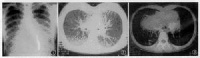

胸部X线检查是诊断肺大疱的最好方法。肺尖部肺大疱表现为位于肺野边缘甚细薄的透亮空腔,可为圆形、椭圆形或较扁的长方形,大小不一,较大的肺大疱中,有时可见到横贯的间隔。多个肺大疱靠拢在一起可

呈多面状。一般不与较大支气管直接相通,无液平,支气管造影剂也不能进入。肺底部的肺大疱,在正位胸片上常常不易见到,有的可以完全位于膈顶水平之下,有的则仅有部分位于膈顶之上,肺大疱壁如不显示为连贯的环状线条影,很易被误认为幕顶状胸膜粘连。巨大肺大疱一般具有张力,在其周围可有一层压迫性肺不张,使疱壁显得较厚,贴近胸壁的可不清楚。附近的肺被推压而引起部分肺不张,肺纹理聚拢,透亮度减低。肺大疱可以相互融合而形成占位很大的肺大疱,形似局限性气胸。肺大疱也可破裂而产生局限性气胸。

透视和呼气相胸片有助于发现肺大疱,因呼气时气体滞留使肺大疱体积显得相对增大,边缘更加清楚。断层对明确肺大疱轮廓和显示周围肺组织的压迫与移位也有帮助。并存小叶性肺气肿时,断层片也可显示肺血管形状的异常。

CT检查可发现胸膜下有普通胸片不易显示的直径在1cm以下的肺大疱。

X线表现

肺野透亮度增加,可见少许细网状结构,肺界限不清,大疱周围可见到受压致密的肺纹影。